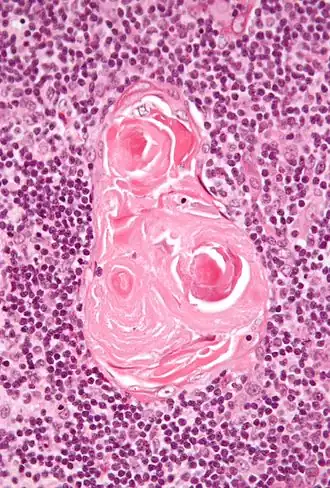

Micrographie des corpuscules de Hassal

Les corpuscules de Hassal, appelés aussi corpuscules thymiques, sont des structures arrondies, éosinophiles, lamellaires et en bulbe d’oignon situées dans la zone médullaire du thymus de l'homme. D'origine endodermique, ces structures épithéliales doivent leur nom au médecin britannique Arthur Hill Hassall (en) qui les a découvertes en 1846[1].

Leur fonction reste encore obscure mais il semble qu'ils peuvent, grâce à la production de la cytokine TSLP (thymic stromal lymphopoietin), intervenir dans le processus inflammatoire.